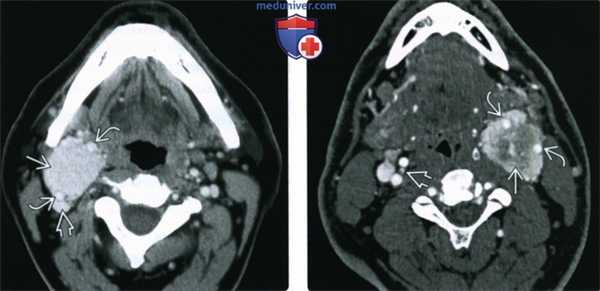

(Слева) КТ с КУ, аксиальная проекция. В области бифуркации правой общей сонной артерии расположено новообразование, равномерно накапливающее контрастное вещество. Опухоль находится между ветвями сонной артерии и смещает внутреннюю яремную вену кзади.

(Справа) КТ с КУ, ранняя артериальная фаза. Опухоль находится в области левой бифуркации и неравномерно накапливает контраст. Она частично заключает в себя сонные артерии, следовательно, относится ко II или III типу по Shamblin. В области правой бифуркации также имеется небольшая параганглиома. Вероятнее всего, заболевание имеет наследственную природу.